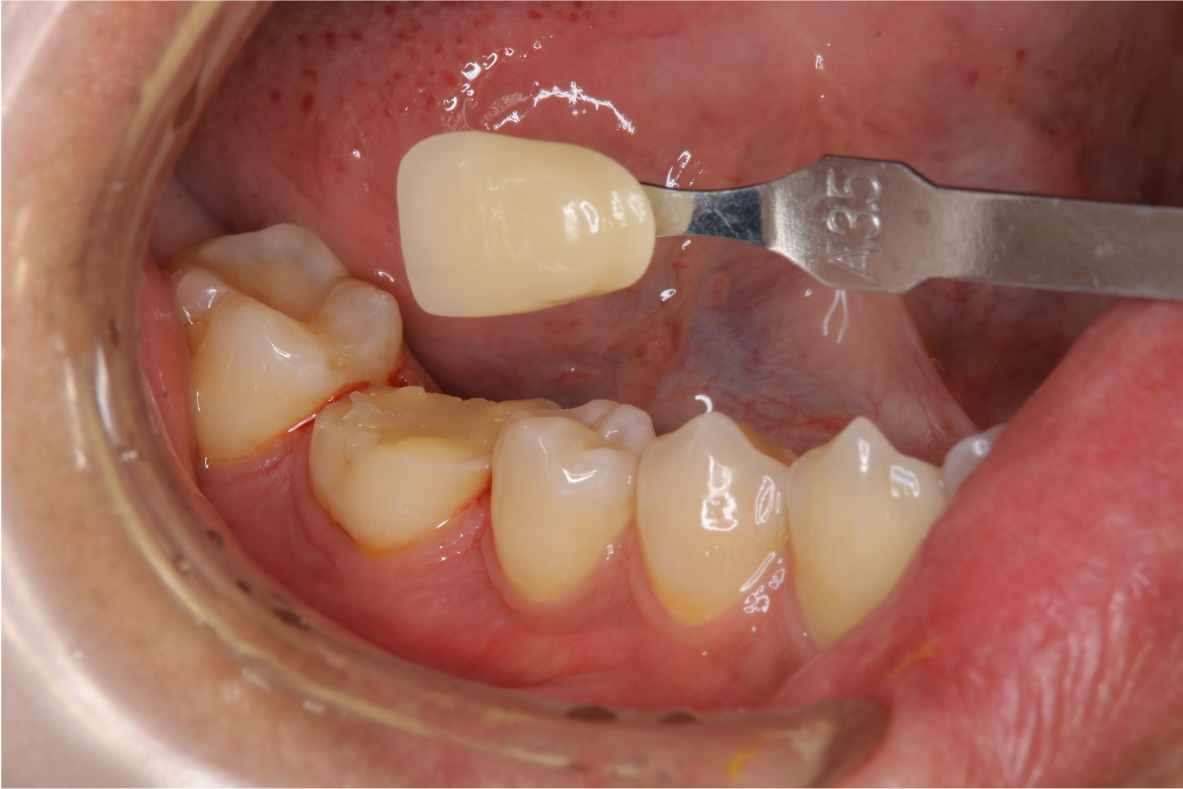

照相比色